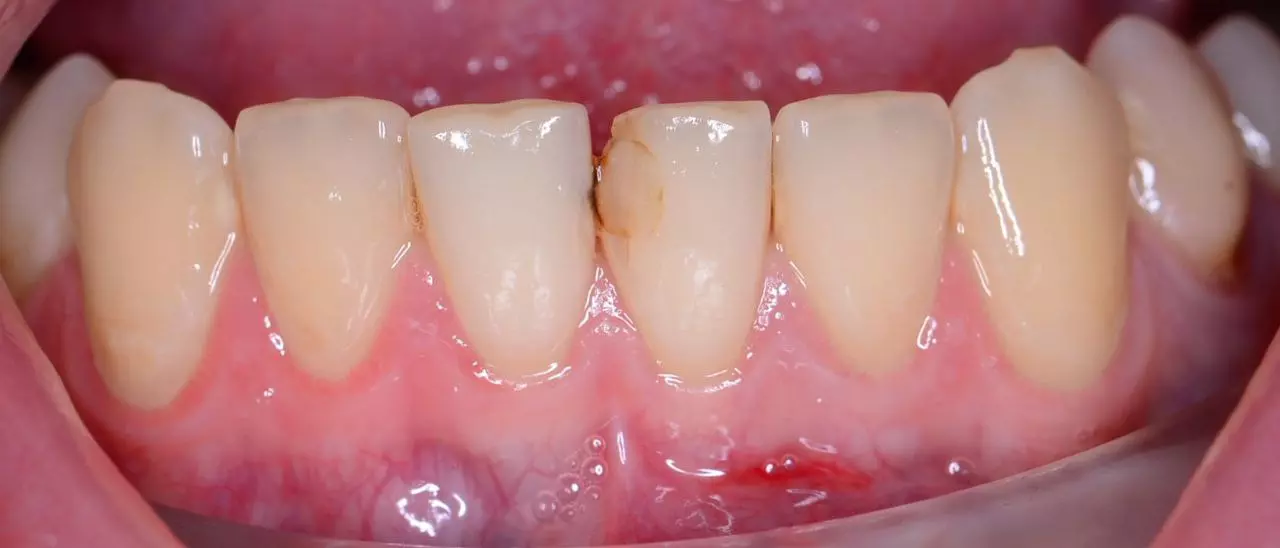

Лікування карієсу

Лікування карієсу 41, вторинного карієсу 31.